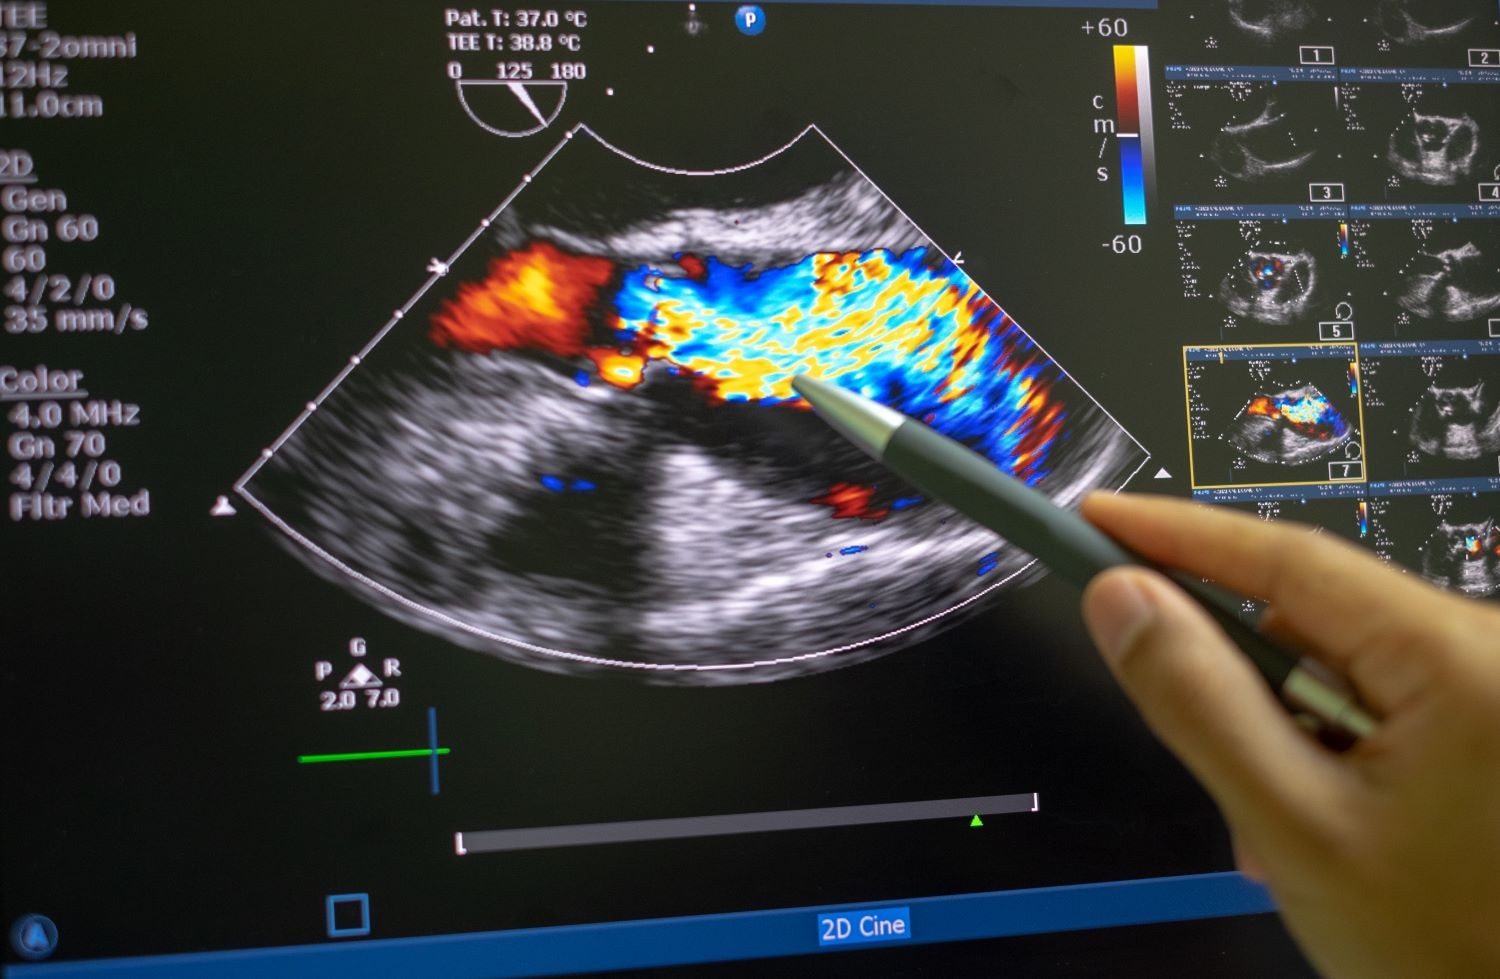

Am Stadtspital Zürich beurteilen wir jährlich mehr als 6000 Patient*innen mit Herzklappenerkrankungen und führen etwa 200 Katheter-technische Klappeneingriffe über die Leistengefässe durch. Damit gehört das Stadtspital Zürich zu den grössten Zentren in der Schweiz für die Behandlung von Herzklappenerkrankungen. Die Beurteilung und die Eingriffe erfolgen in enger Zusammenarbeit mit der Klinik für Herzchirurgie. Erfahrene Kaderärzt*innen stehen Ihnen rund um die Uhr zur Verfügung.